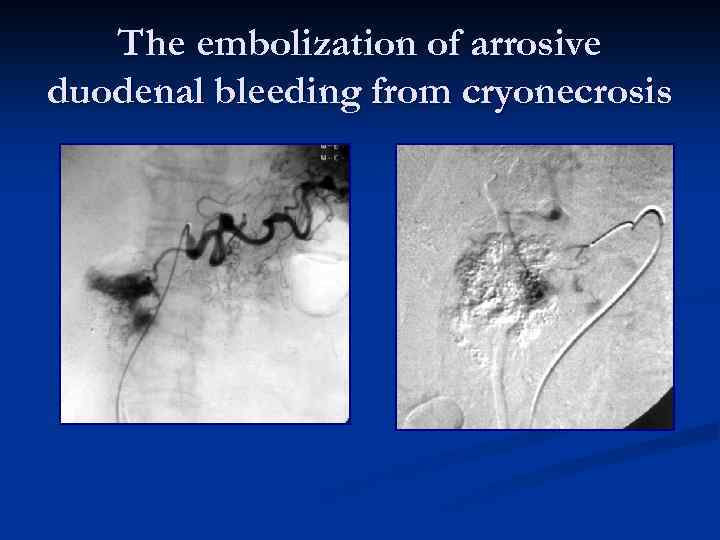

The embolization of arrosive duodenal bleeding from cryonecrosis

The embolization of arrosive duodenal bleeding from cryonecrosis